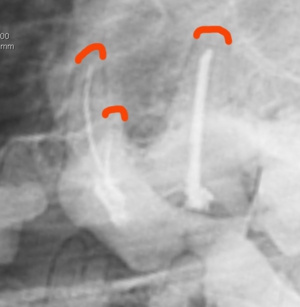

青:アクセスポイント 緑:破折部位

青:根管のアクセスポイント

各々の根管にファイルを挿入し根管長を測定

ペーパーポイントにて根管を乾燥

ポータブルレントゲンによる術中写真

術後の写真 充填( 赤ラインは根先部 )

麻酔なしのレントゲンにおいては2本が重なり一本に見えることもあります。